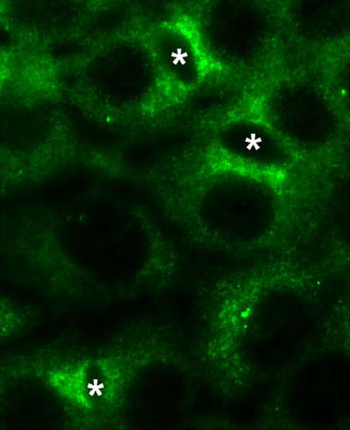

Figure 1 : Images par contraste de phase d’un épithélium de cellules WIF-B9 et par immunofluorescence de la protéine ATP7B excrétant le cuivre vers la bile dans ces cellules.

En s’associant pour former un épithélium, les WIF-B9 se polarisent et créent entre elles des espaces mimant le canalicule biliaire (*) ; noyaux (n).

Le milieu de culture ne contient que le cuivre basal. La protéine est détectée dans le Golgi, entre les noyaux et le canalicule, où elle joue son rôle basal de transfert du cuivre.